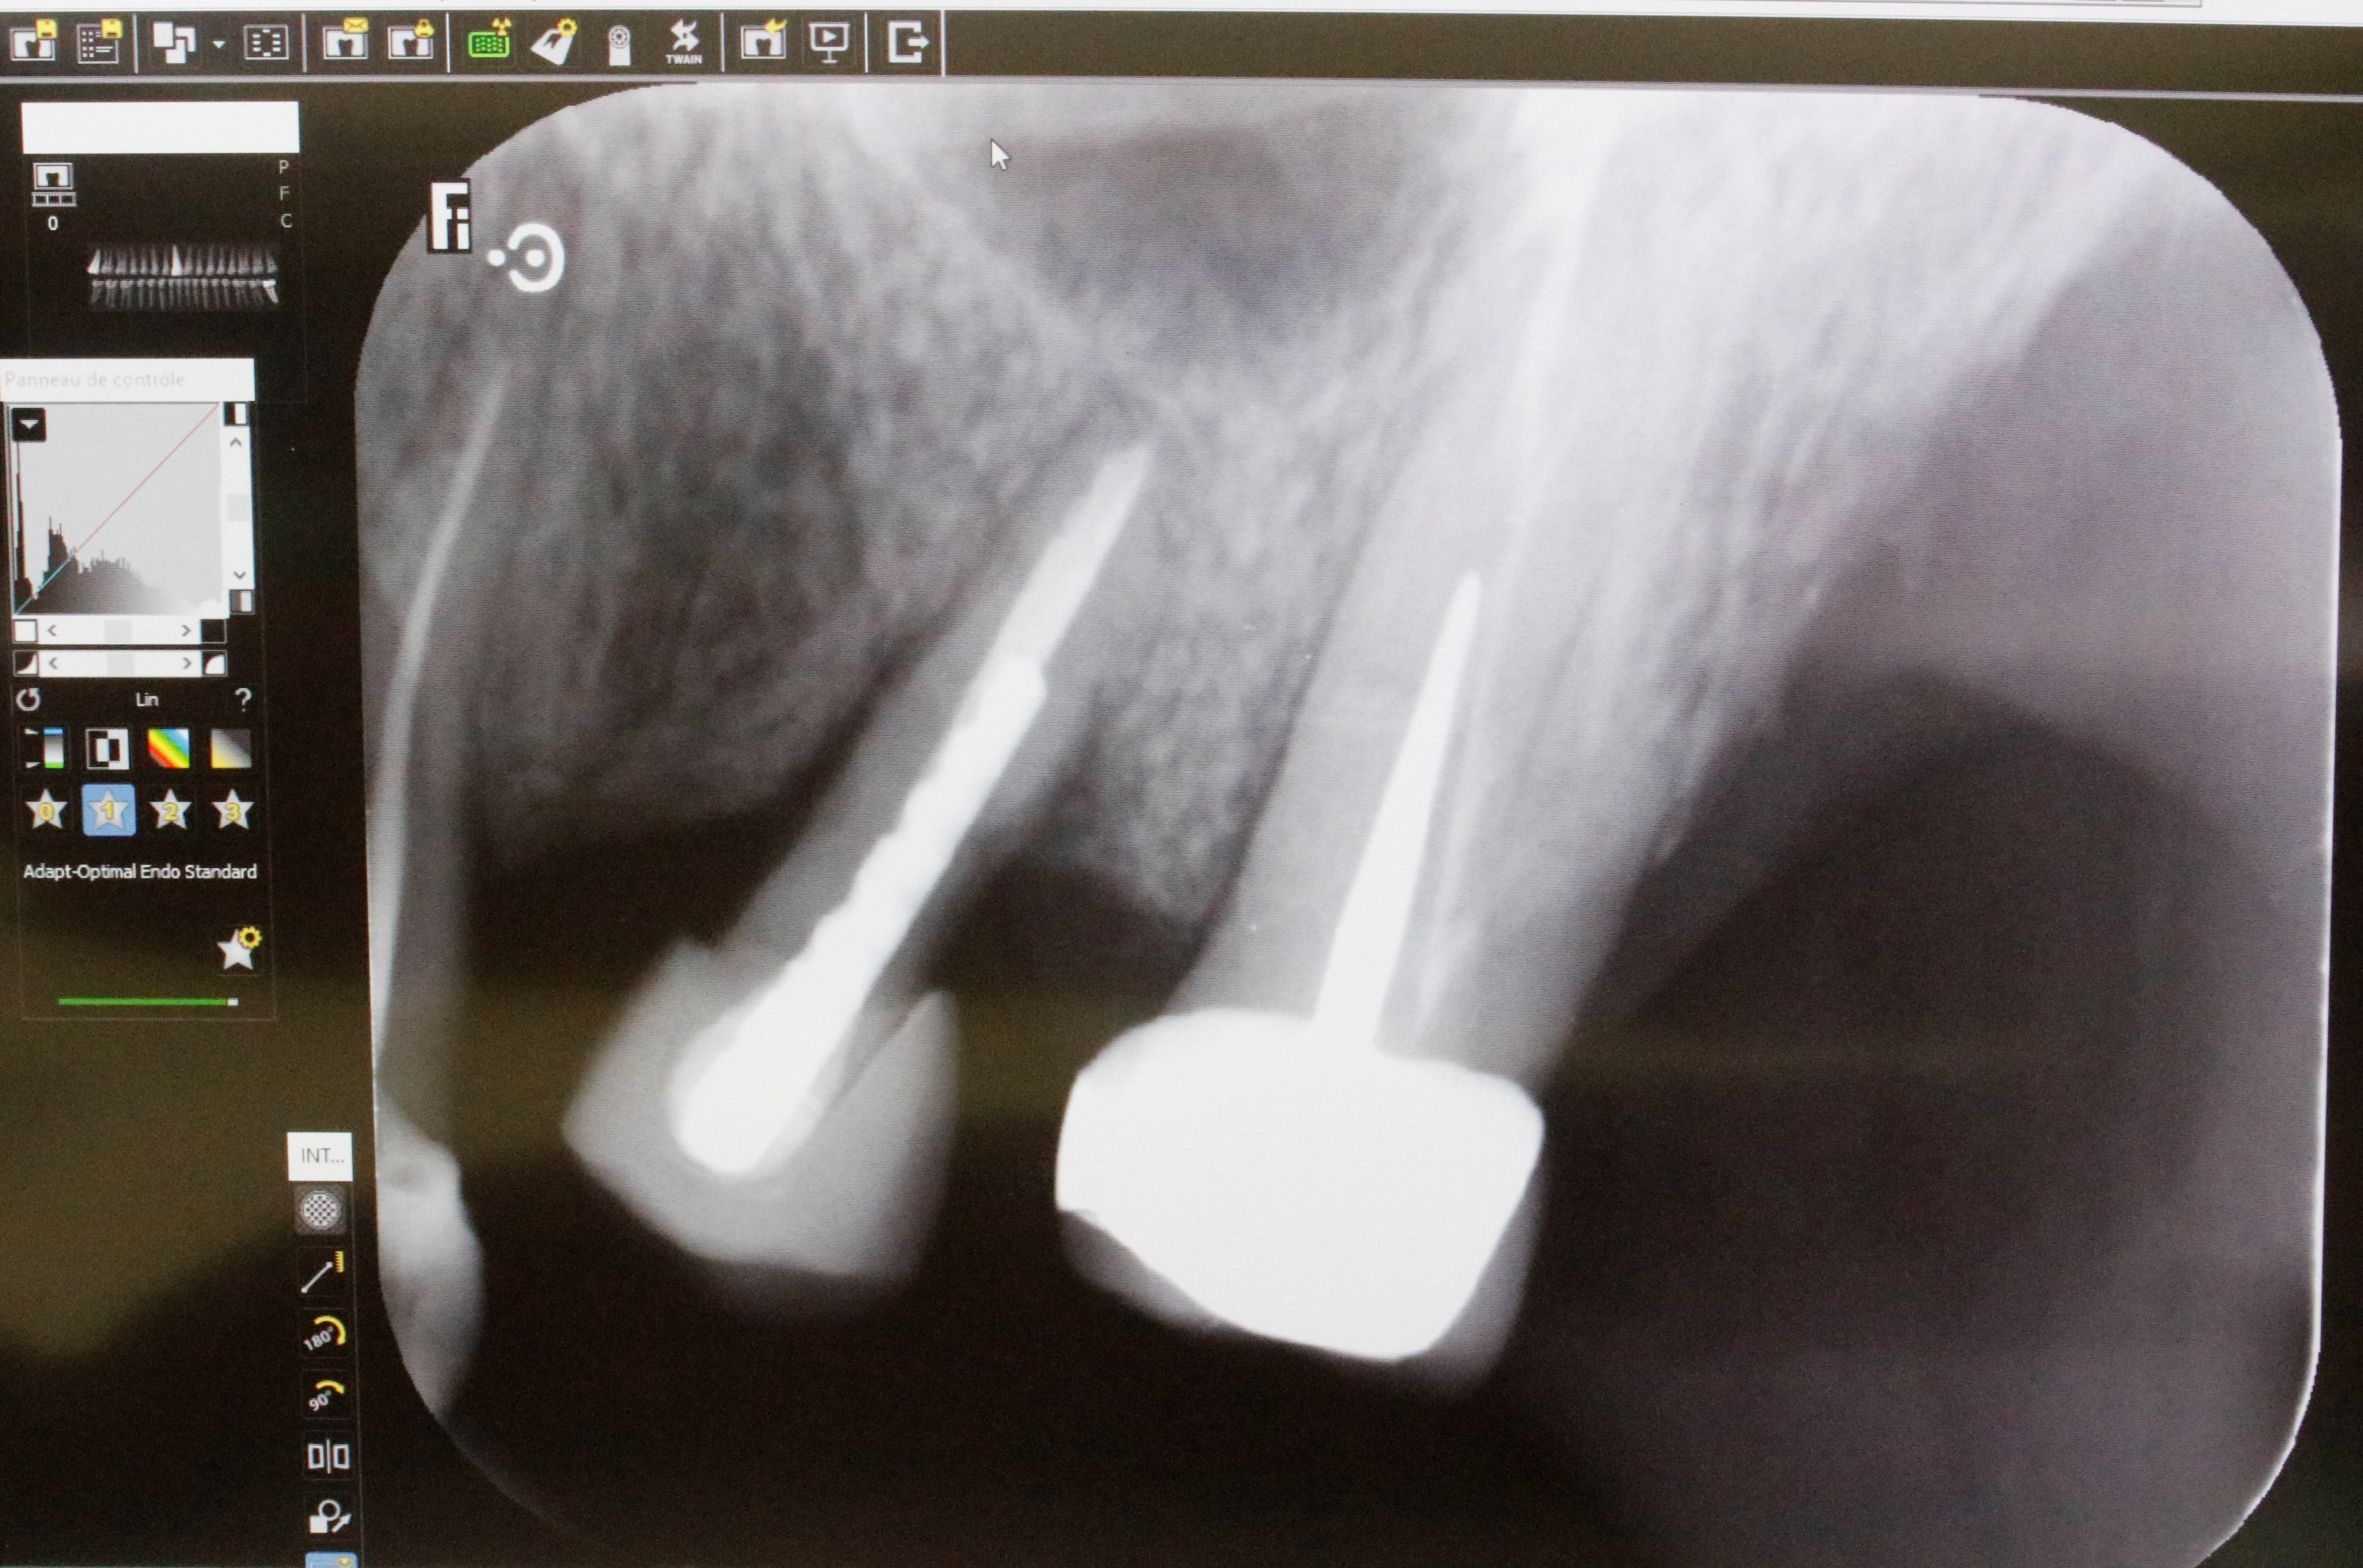

ERI réalisée il y a 25 ans

Historique :

- choc

- le praticien dévitalise

- lésion toujours présente

- il décide d’extraire et de réimplanter

Aujourd’hui résorption. Je me demande si ils n’ont pas foutu un plombage à l’apex dans le temps. Le plombage aurait migré. D’où la tâche violette sur la muqueuse